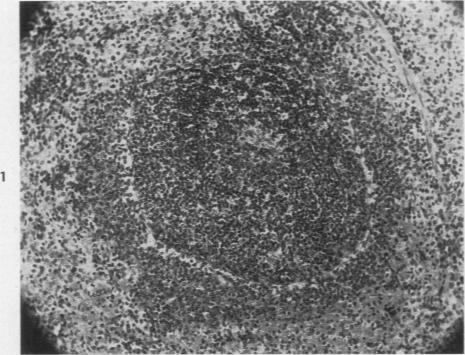

A Histologic Study of the Reaction in the Hamster Spleen Produced by the Virus of Colorado Tick Fever.

Am J Pathol. 1947 Mar;23(2):217-25.